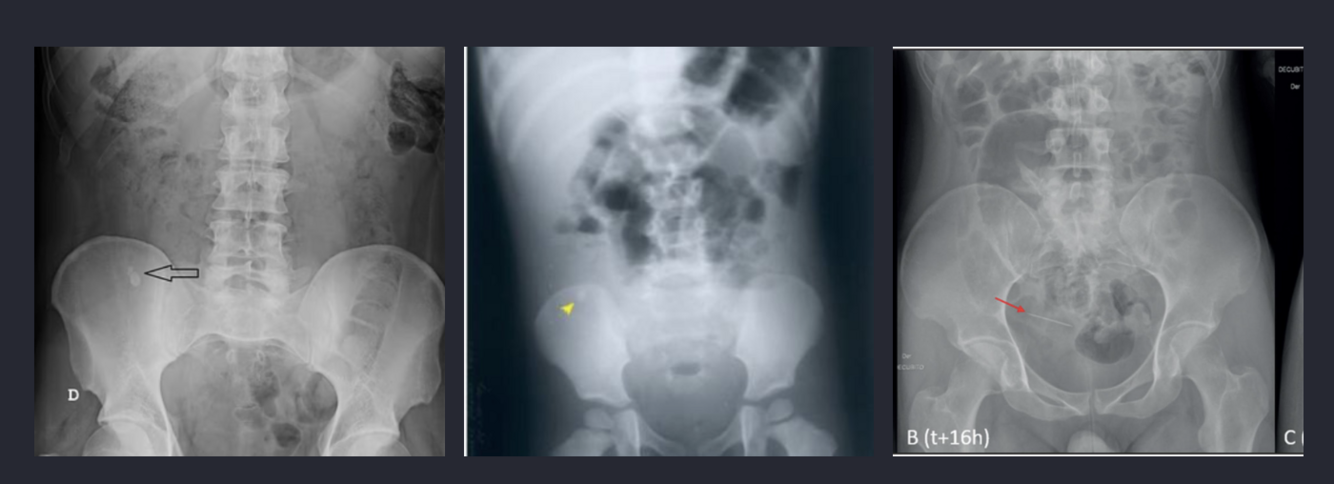

* Rx de abdomen de pie y decúbito: ya no se usa

1. Fecalito que si se localiza FID y permanece inmovil en ambas proyecciones se atribuye a ap, cuando más de 6 horas de evolución se borra psoas en RX

2. Cuadro de obstrucción intestinal

3. Cuerpo extraño en apéndice